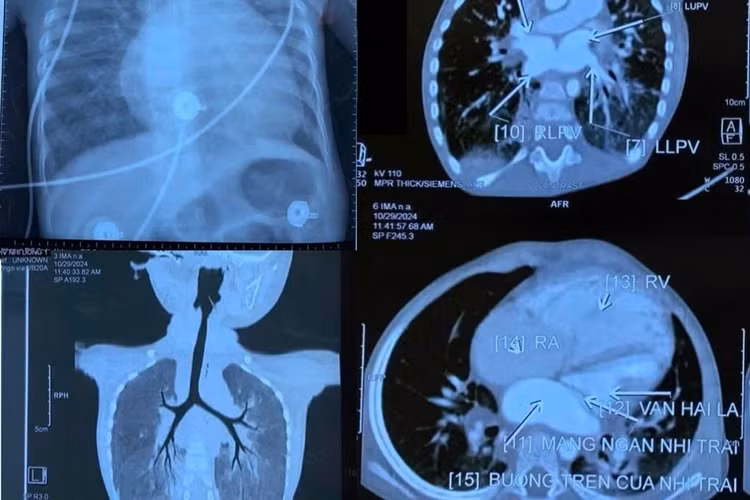

ThS.BSCK2 Ngô Kim Thơi, Trưởng khoa Ngoại Tim mạch, Bệnh viện Nhi Đồng 1 cho biết, kết quả làm các xét nghiệm, siêu âm tim, các bác sĩ phát hiện bệnh nhi có nước tiểu đỏ (triệu chứng khi dùng thuốc trị lao phổi kéo dài), đồng thời có dị tật tim bẩm sinh nặng - dị tật màng ngăn nhĩ trái ở tim.

Trong các dị tật về tim, khi màng ngăn nhĩ trái có tắc nghẽn mà không được phát hiện, xử trí kịp thời sẽ có nguy cơ đột tử. Nếu phát hiện sớm, được phẫu thuật, tim có thể phục hồi lại bình thường.

Do bệnh nhi không được chẩn đoán sớm, khiến trái tim gánh chịu hậu quả khá nặng nề: Sức co giãn cơ tim của bé giảm mạnh, áp lực động mạch phổi cao.... Bệnh nhi cần phải phẫu thuật khẩn, nếu không sẽ ảnh hưởng tới tính mạng.

| Dị tật tim bẩm sinh, màng ngăn nhĩ trái của trẻ trên phim chụp - Ảnh BVCC |

ThS.BSCKII 2 Nguyễn Trí Hào, Trưởng khoa Tim mạch cho biết, quá trình phẫu thuật, dù bé được gây mê sâu, nhưng áp lực động mạch phổi vẫn rất cao, trái tim đập rất yếu song ê-kíp đã cố gắng phá bỏ hoàn toàn màng ngăn nhĩ trái ở tim để cứu bé.

Theo BS Hào, dị tật màng ngăn nhĩ trái ở tim rất hiếm gặp, với tỷ lệ 1/1.000 trường hợp. Mỗi năm, Bệnh viện Nhi đồng 1 chỉ tiếp nhận một trẻ mắc bệnh này. Đáng chú ý, trẻ dù bị dị tật ở tim nhưng sẽ có tình trạng bị ứ máu lại ở phổi, nên dễ bị chẩn đoán nhầm thành bệnh ở phổi nếu người điều trị không có chuyên môn sâu về tim mạch.